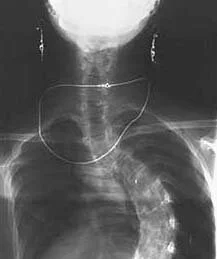

As I got further into my project, I felt the need for better source materials, and I began to collaborate with orthopedic surgeons and radiologists to have medical images made for the purpose of art. It was exciting to art-direct my first x-ray! Keeping my earrings and gold chain on (instead of, as usually happens, being made to take off everything metal) made me feel triumphant, and made the x-ray image more personal. Working with doctors as an artist and fellow professional, I felt respected and seen in a way I never had as a patient.